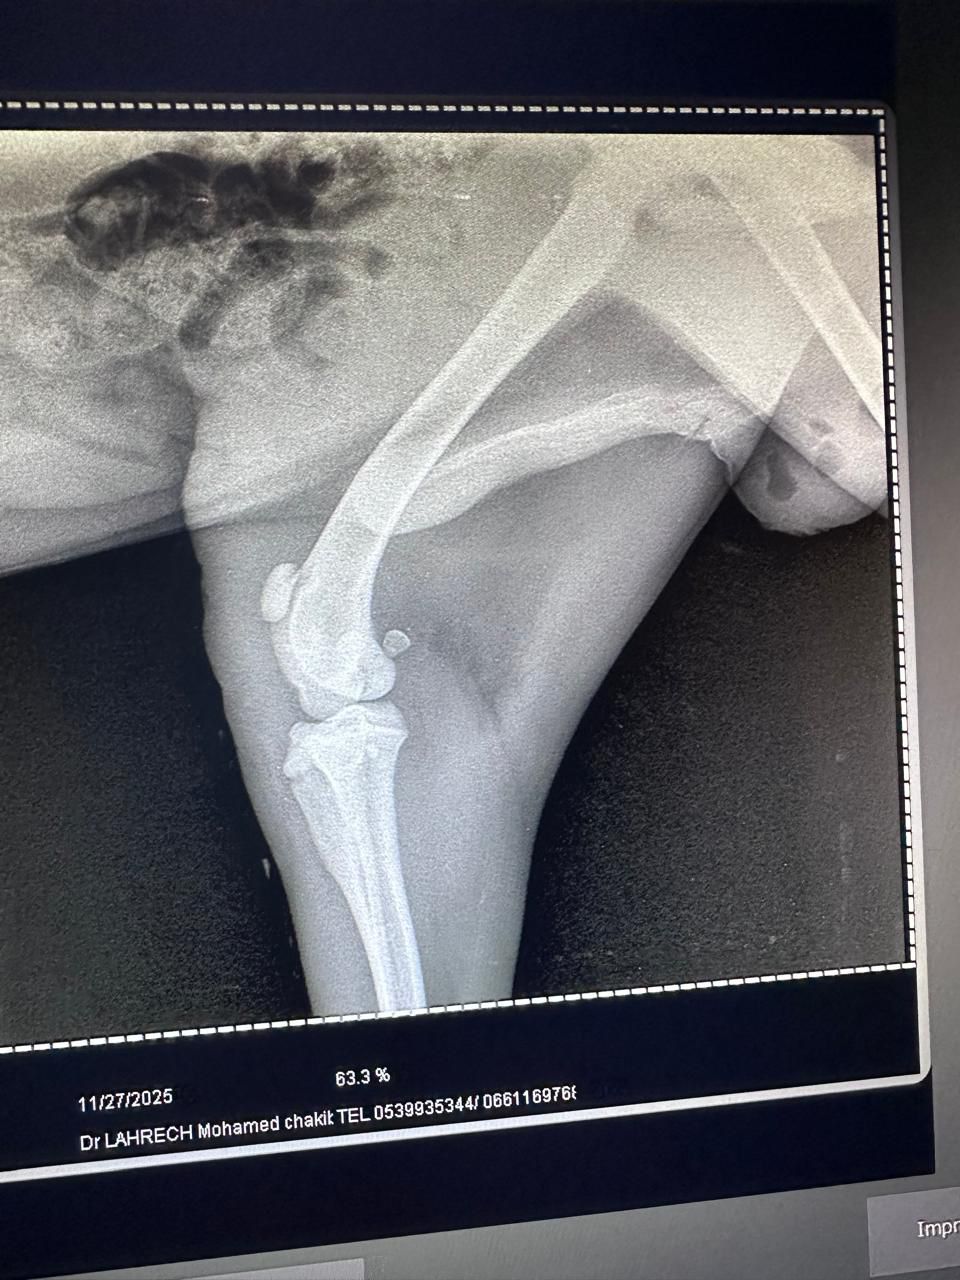

Rami trafił do naszych zaprzyjaźnionych ludzi na miejscu. Tych samych, których znacie, z którymi współpracujemy od dawna i dzięki którym setki zwierząt dostały szansę. Na jego ciele widać liczne obrażenia. Nie wiemy jeszcze, co dokładnie jest uszkodzone, bo bez diagnostyki nie da się tego ocenić. Pilnie potrzebne jest RTG, badania i dalsze leczenie. Potem kastracja, jeśli tylko jego stan na to pozwoli.